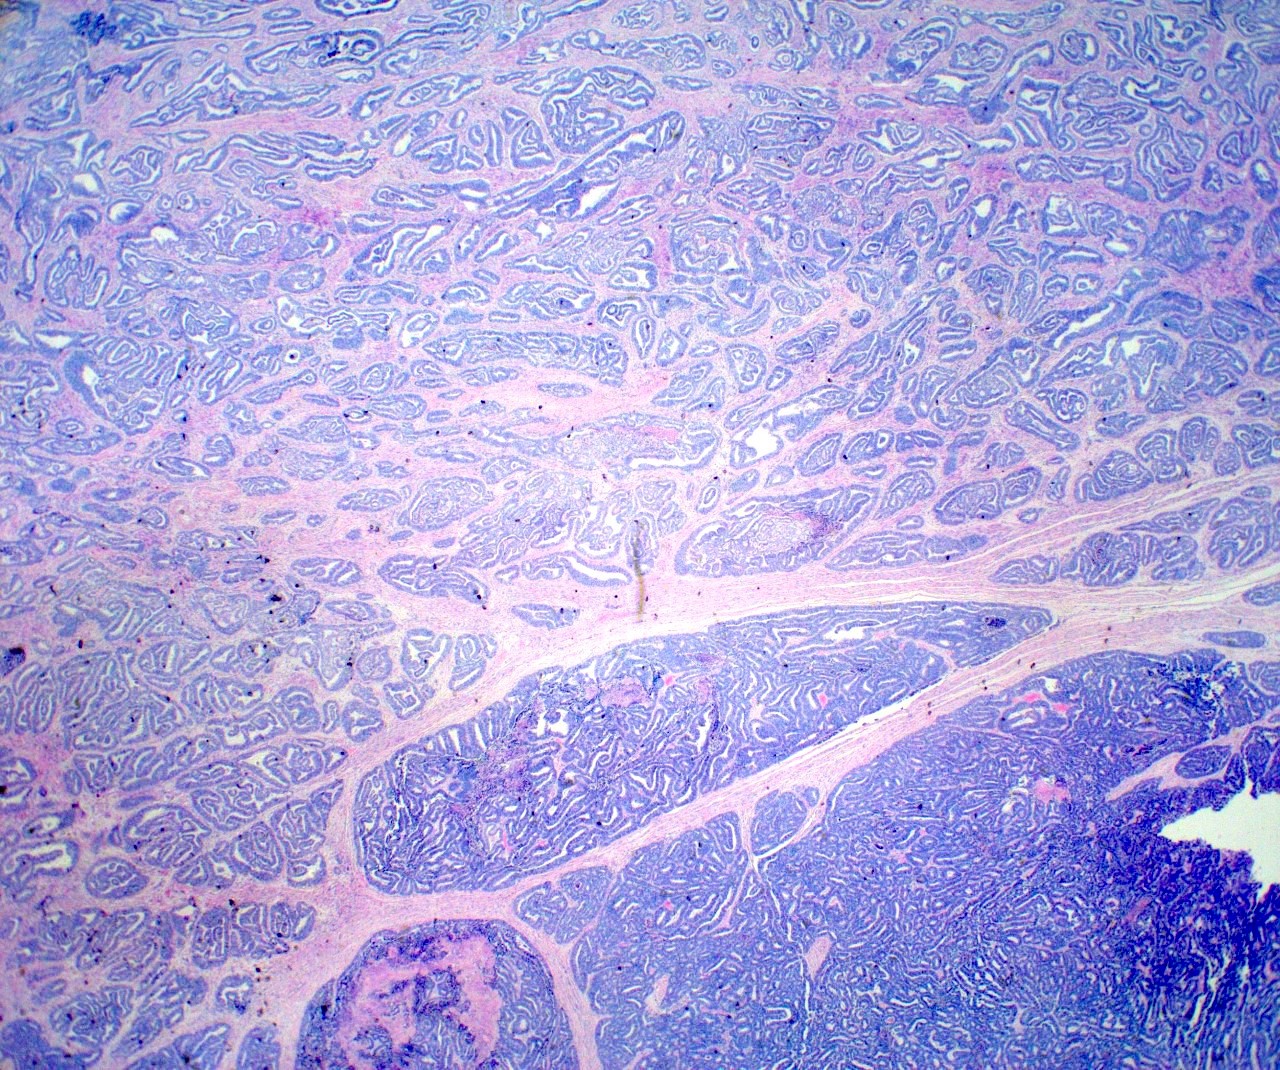

- Variety of histologic patterns that may be present within the same tumor

- Most frequently small tubules with ductal / glandular growth

- Papillary, solid growth, trabecular, retiform, sex cord-like, sieve-like, glomeruloid and spindle cell areas have all been described

- Luminal eosinophilic secretions are characteristic but not always identified

- Tumor cells can be flattened, cuboidal or columnar with mild to moderate cytological atypia

- Clear cell features can be seen but are less common

- High grade cytological atypia is usually not a predominant feature

- Nuclei show vesicular chromatin and nuclear grooves

- Sarcomatoid transformation has been seen in rare instances

- Squamous, ciliated or mucinous differentiation (metaplasia) are not present and there are no associated mesonephric remnants (J Clin Med 2021;10:698)

Microscopic (histologic) images

Contributed by Daniel Graham, M.D., Adele Wong, M.B., B.Ch., B.A.O. and Lucy Ma, M.D.